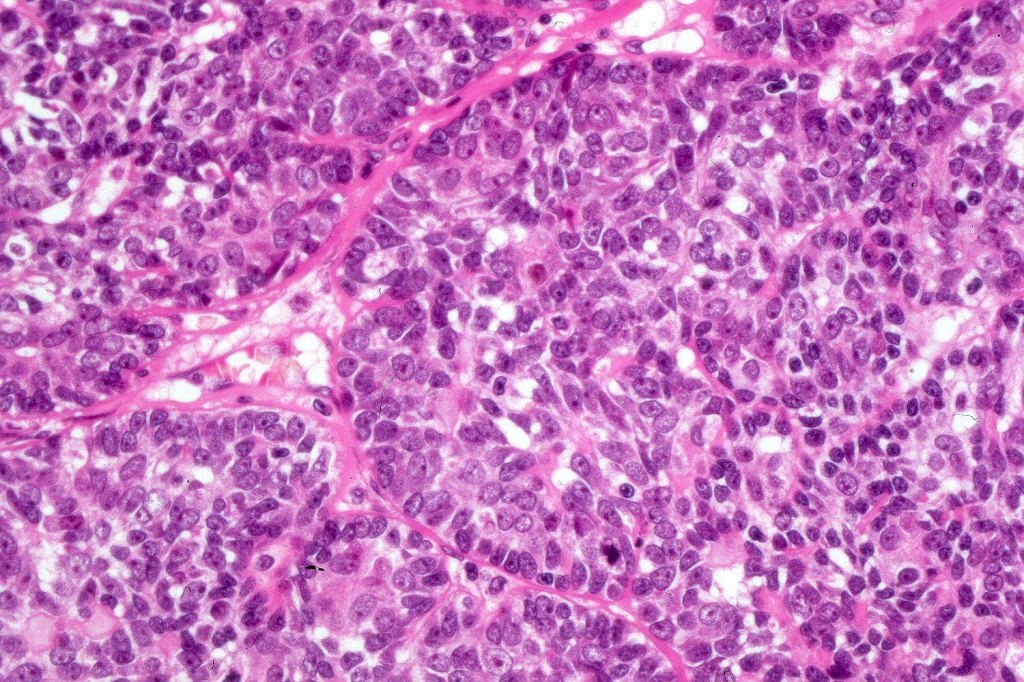

Histological features

•Malignant component shows loss of dual cell population, increased mitotic activity, atypical mitoses & necrosis

•Diagnosis depends on H/E rather than IHC

•The alternative classification into low grade (with only mild atypia and increased mitotic activity) and high grade variants has some merit although in any individual case this can be hard to apply unless the whole tumor has been sampled and is of uncertain biological merit.